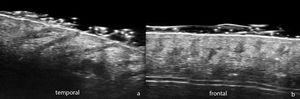

Respecto a LPP y AFF, hay un estudio específico del 202023 en el que se evaluaron 10 pacientes con LPP y 2 con AFF y se describieron células inflamatorias en epidermis próxima al infundíbulo anexial en casi la mitad de los casos, hallazgo consistente con la histopatología de estadios tempranos18,23. En lesiones de larga duración se observaron vasos sanguíneos dilatados, aumento de fibras dérmicas gruesas mal definidas y fibrosis perifolicular extensa (fig. 4).

A) Placa alopécica cicatricial en área interparietal. B) Tricoscopia: eritema, hiperqueratosis perifolicular y tufting folicular. C) MCR: hiperqueratosis infundibular con material blanquecino que rellena el infundíbulo del folículo piloso y rodea el tallo piloso D) En la dermis se observa un aumento del número de fibras dérmicas, mal definidas y gruesas.